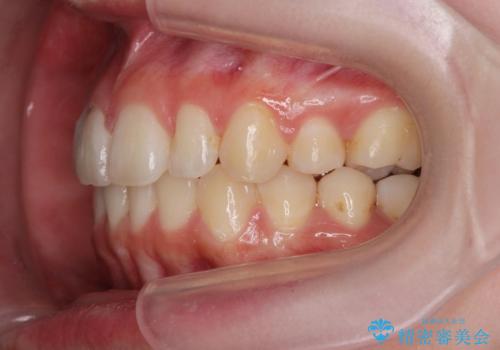

少し時間はかかりましたが、しっかりと綺麗な歯並びに仕上げることができ、大変喜んでいただくことができました。